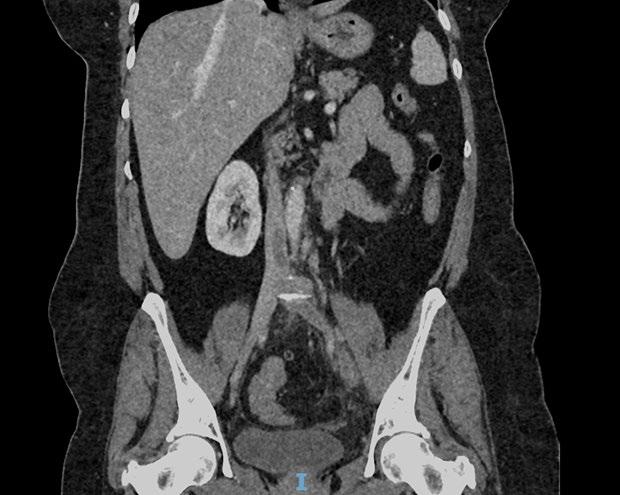

Create a flipbook